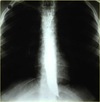

19

Raised hemidiaphragm (phrenic nerve injury) due to lung cancer